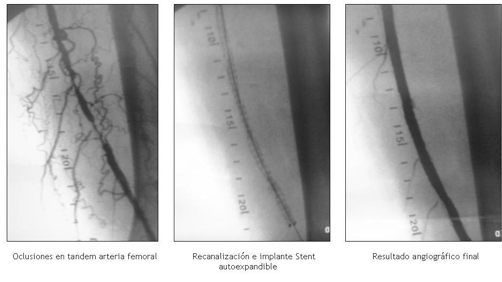

Recanalización Femoral Izquierda con Stent